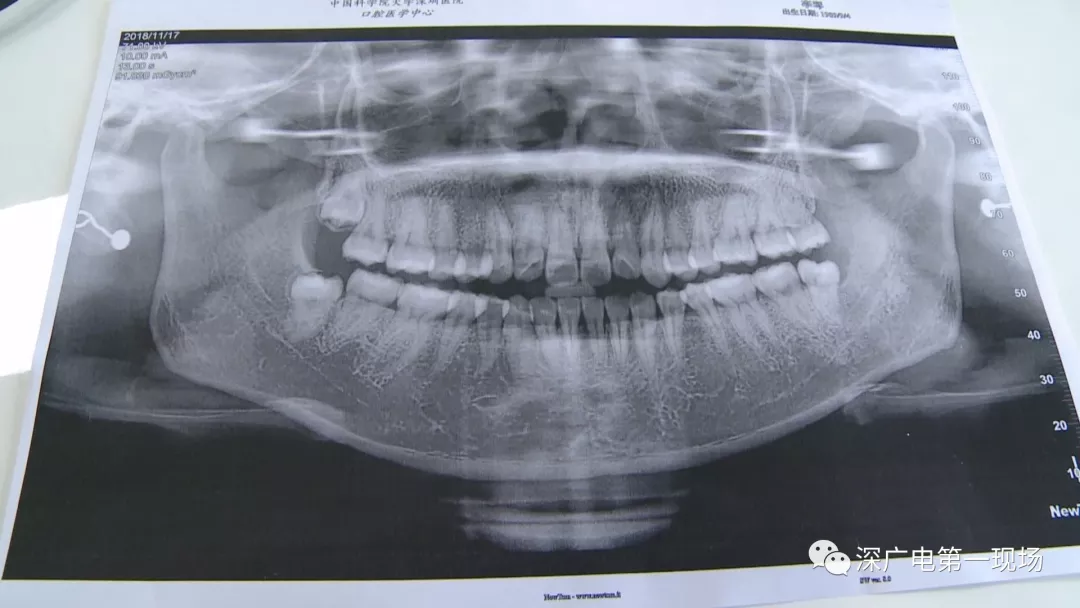

于是,李女士來到中國科學(xué)院大學(xué)深圳醫(yī)院口腔科,醫(yī)生經(jīng)過一番檢查之后,做了智齒拔除手術(shù),共花費(fèi)了一千多元。

針對李女士的情況,醫(yī)生介紹,當(dāng)時(shí)要想拔出李女士的這顆智齒,難度還是很大的,屬于復(fù)雜智齒的拔除術(shù)。她的風(fēng)險(xiǎn)在于距離神經(jīng)管近,同時(shí)這顆牙齒完全埋在牙床最后的位置,直接往外拔,會(huì)加大頜骨的風(fēng)險(xiǎn),因此需要先切開,讓牙齒暴露后,切小再慢慢地拔出。